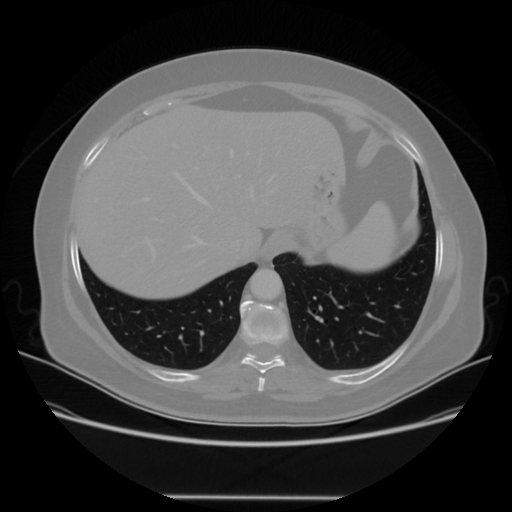

Image Grid

4Γ—3 grid: Rows show different image types (Original NATIVE, Reconstructed NATIVE, Original VENOUS, Generated VENOUS), Columns show windowing techniques (No Window, Lung Window, Mediastinum Window)

Original NATIVE CT scan (input)

Full window (WL 1023.5, WW 4095 β†’ Low βˆ’1024, High +3071)

Actual HU range: [-1024.0, 918.0]